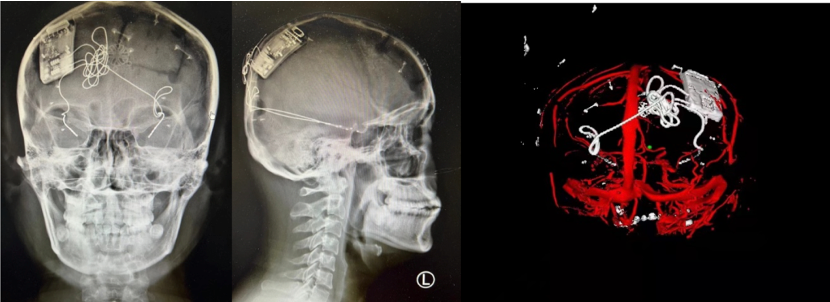

On March 9, 2022, the stereotaxic and functional brain disease team led by Professor Zhao Guoguang, President of Xuanwu Hospital of Capital Medical University, and Professor Shan Yongzhi of Neurosurgery, successfully treated a patient with refractory epilepsy (bilateral temporal lobe) with implantation of the closed-loop reactive neurostimulation system Epilcure™. The operation went smoothly, and all the indicators of the intraoperative stimulator worked normally. The postoperative reconstruction showed that the electrode position was accurate and the EEG signal was clear. The successful completion of this implantation operation marks the first patient enrollment in the Epilcure™ National Medical Products Administration (NMPA)-registered clinical trial led by Xuanwu Hospital.

The patient was male and was diagnosed with bilateral temporal lobe epilepsy after admission. This type of epilepsy is a relative contraindication to craniotomy, and traditional treatment is not effective in the case of uncontrolled medication. The closed-loop reactive neurostimulation system is an important clinical application of "brain-computer interface". This technology uses artificial intelligence chips to be implanted in the skull, intracranial electrodes are implanted into the brain, and the EEG rhythm is monitored day and night without interruption. The occurrence of epilepsy, that is, the activation of exogenous interference rhythms, directly blocking the formation of epilepsy in the epileptogenic foci, and accurately controlling the activity of the loop. This new technology has brought good news to patients with epilepsy in multifocal or functional areas. The foreign product was approved by the US FDA in 2013, but it has been used as a "neck stuck" technology for long-term technical blockade and restrictions in China. The implantation of this system means that the "brain-computer interface" high-tech product with independent intellectual property rights has reached the final step before full-scale clinical use after the arduous efforts and research of the domestic clinical and basic research teams.